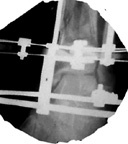

Date: Thu, 14 Dec 1995 17:48:46From: hwb@eideti.com (Bill Burman)Of course what I have to say has to be taken with a mountain of salt as Ihave not practiced orthopaedics for 5 years.What I would do at this point is hike out the 5 mm diaphyseal pin. I can'tbelieve it is doing much. I would wait a few more weeks for that pin tractto properly clean itself and seal up. Hopefully it has not been infected.At that time I ought to have pretty good consolidation of themetaphyseal-epiphyseal fractures. I would remove from the ends of the boneany hardware which would block the placement of a reamed interlockingtibial nail. Large reduction forceps and possibly strategically placedsteinman pins would be used to protect against the possibilty ofmetaphyseal-epiphyseal refracture during nail placement. The nail needs tobe carefully started as high as possible and more lateral than usualbecause of a valgus tendency for nailings of proximal tibia fxs.If at this time, I did not see much in the way of diaphyseal callus thenprior to nail placement, I would try to do a closed intramedullary iliacbone grafting with chest tube ala Chapman, JBJS 62A 1004 1980. I realizethis technique was meant for segmental defects of the femur but this mightbe an application for it as well. If I couldn't get much graft in this way,I would put it in posterolateral - if that did not jeopardize the free flapin some way.*****************************From: EDCCYANG@aol.comDate: Thu, 14 Dec 1995 22:16:30 -0500You are to be commended for what you've done so far. It sounds like thetibia is well aligned and the soft tissues are healed. Now you just have toget the bones healed.I have extensive experience with the hybrid exfix but never have I seen atibia this shattered. (or maybe once)Now I would try the exogen unit, if you have not done so already. This isthe ultrasound device which has been working great for us! Their telephone# is 1-800-836-0849.I would hold him in the external fixator as long as the pins are clean.Hopefully, some of the fractures will heal and you can deal with only one ortwo nonunion sites. Consider plating the fibula and getting the fibulahealed, either simultaneously with a fib-pro-tib operation, and /orposterolateral bone graft. I have done all of the above to get tibiae toheal.Edward Yang, MDElmhurst HospitalMount Sinai****************Date: Fri, 15 Dec 1995 10:21From: Jeffrey Anglen Bill, for a guy who hasn't practiced clinically for 5 years, you seem tohave a pretty good grip on treating tibia fractures. The only thing I woulddisagree with is conversion to an intramedullary nail after this period oftime. I would be too afraid of intramedullary infection from a pin site,even if the pin sites looked OK. I don't know if the risk is the same withhybrid fixators as it is with traditional half-pin fixators - that might makean interesting study - perhaps someone with more experience withhybrid fixators has a better feel for the relative risk between pin andwire sites.I would continue with hybrid fixation, a little weightbearing and earlybone graft of the diaphysis posterolaterally. I have no experience withthe accordion technique.How about you guys at Harborview? Any thoughts on this tibiafracture?****************Date: Sat, 16 Dec 1995 11:45:10 +0530 (IST)From: "Dr.ML Parihar" the accordion manouevre does not work. to my knowledge this is nowuniversally accepted, especially in the treatment of non-unions. anyonedisagree?for a comminuted fracture of the tibia why not consider atibia-pro-fibula grafting as described by harmon. while on the subject ofbone grafting i would like to hear fromsurgeons who have used bone marrowinjections for the treatment of nonunion or delayed union.how much to be aspirated? from where?where do you inject? into the fracture site or in a cuff fashion aroundthe fracture site? Dr. Mangal Parihar**************************Date: Sat, 16 Dec 95 22:04:09 +0500From: "Alexander N. Chelnokov" Hi> I have not received any further comments/suggestions on the comminuted> tibia case since posting the images of the xrays. There has been> considerable useful discussion of posting images to be easily viewed> in various manners.Sorry but I missed when you pointed the name and location of the image so plsrepeat...> I did institute the "accordion" technique of .25 mm compression at> 6 am and noon; then .25 distraction at 6 pm and midnite.We use another schedule - 2 weeks of distraction 0.5mm/day and then2 weeks of compression 1 mm/day...> I also started 10 pound weight bearing.I do not limit weigth-bearing. More exactly, patient should load his legas he can. In case of extra-articular fractures of course.> I'd like to bone graft it but I'm not sure> where to put the bone graft because there are so many pieces.Do think about marginal corticotomy and slow tension of fragments to bridgegaps?*************************Date: Sun, 17 Dec 95 21:45:18 -0600From: "Andrew H. Schmidt" After seeing the images, I congratulate Tom on his management of the casethus far. Our general philosophy at Hennepin County is that once externalfixation is chosen as the treatment, it should be continued to union. Whenpossible, we will convert to a nail within the first couple of weeks, butnot beyond this because of the concern for infection.In my experience with either plateau or plafond fractures plus diaphysealextension, the metaphyseal fractures heal and it is the diaphysealcomponent that requires grafting. I have several times removed the hybridfixator, curretted the pin sites, performed an open autogenous grafting,and reapplied a new half-plane unilateral fixator to the diaphysis. Ofcourse, if the hybrid frame was still needed I would not replace it.However, I find the circular hybrid frames to be such a hassle to take careof, and the patients dislike them so much, that if the juxta-articularfractures are healed, I go ahead and convert to a simpler fixator. So, that remains my two-cents worth, which I thought I'd post to the wholegroup this time since this case has sparked so much interest.AndyAndrew H. Schmidt, M.D.Staff Physician, Hennepin County Medical CenterClinical Instructor, University of Minnesota******************************Date: Tue, 19 Dec 1995 12:31:57 -0500From: hwb@eideti.com (Bill Burman) I see from the discussion that perhaps I am too aggressive and need tolearn how to relax.I am learning some new things here. Dr. Ed Yang made a plug for ultrasoundstimulation - Exogen. Here is the abstract of an article published in theJ Bone Joint Surg Am 1994 Jan;76(1):26-34 by the San Antonio group(Heckman, Ryaby, McCabe J, Frey JJ, Kilcoyne RF). The study was paid forby Exogen.TI - "Acceleration of tibial fracture-healing by non-invasive, low-intensity pulsed ultrasound."AB - "Sixty-seven closed or grade-I open fractures of the tibial shaft were examined in a prospective, randomized, double-blind evaluation of use of a new ultrasound stimulating device as an adjunct to conventional treatment with a cast. Thirty-three fractures were treated with the active device and thirty-four, with a placebo control device. At the end of the treatment, there was a statistically significant decrease in the time to clinical healing (86 +/- 5.8 days in the active-treatment group compared with 114 +/- 10.4 days in the control group) (p = 0.01) and also a significant decrease in the time to over-all (clinical and radiographic) healing (96 +/- 4.9 days in the active-treatment group compared with 154 +/- 13.7 days in the control group) (p = 0.0001). The patients' compliance with the use of the device was excellent, and there were no serious complications related to its use. This study confirms earlier animal and clinical studies that demonstrated the efficacy of low-intensity ultrasound stimulation in the acceleration of the normal fracture-repair process."Also, Dr. Parihar mentions bone marrow injection. In CORR 313 8-18, 1995,Dr. John Conolly of Orlando, FL writes :TI - "Injectable Bone Marrow Preparations to Stimulate Osteogenic Repair."AB - "The great versatility of bone marrow transplants based on stem cellactivity has been demonstrated successfully for a variety of previouslyuntreatable hemopoetic conditions. Autologous bone marrow delivered bypercutaneous injection or by a direct transplant as a composite graft alsohas proven effective for osteogenic stimulation in a series of 100 skeletalhealing problems, including delayed unions and nonunions of fractures,arthrodeses, and bone defects. The efficiency of marrow to form bone can beincreased by a number of methods, including differential centrifugation andcomposite grafts of marrow with demineralized bone matrix and othercarriers or stimulatory factors."Dr. Connolly concludes his article by saying :"Marrow and marrow composite grafts, in this author's experience during thepast 8 years, essentially have eliminated the need for open harvesting anddelivery of autologous bone grafts to stimulate osteogenic repair ofdelayed unions, nonunions, arthrodeses and bone defects."Any references for the Ilizarov "accordion maneuver"?***************************Date: Tue, 19 Dec 1995 14:11:27From: hwb@eideti.com (Bill Burman)I am transmitting another opinion received via the HWB BBS fromDr. Joldas KuldjanovVisiting Professor at Detroit Medical CenterProfessor of Orthopedics & TraumaUniversity of Tashkent, UzbekistanRe: comminuted tibia fxThus far, there appears to be no sign healing because of local factors, thehigh energy of trauma, stripping of periosteum, soft tissue damage and poorcontact of bone. I would have initially fixed the fracture with a four ringIlizarov fixator. 2 rings in metaphyseal zones (distal and proximal) and 2rings in the diaphyseal region for the purpose of interfragmentarycompression.The location of wound and soft tissue damage is unknown to me. It is mostlikely anteromedial ?At this point, I would perform open reduction and internal fixation offibula with a long semitubular plate. I would add 2 more rings to thefixator to bring about reduction and interfrag compression of the tibialcomminution. The type of fixator is immaterial but interfrag compressionwould be accomplished by olive wires. Also, I would add bone graft andplacement of this would be in accordance with the location of soft tissuedamage. Weight bearing should be as tolerated and there should be cautionabout the possibity of equinus. I am not too worried about pin tractinfection. These smaller pins can be easily replaced. I would use theaccordion technique in the event of atrophic non-union.Best regards and best wishes with the management of this very difficult case.***********************Date: Tue, 19 Dec 1995 22:03:13 -0500From: OTS1@aol.com RoyI am somewhat amazed at all this discussion, but find it fascinating. Iwould treat this guy to completion with the circular frame until thearticular and metaphyseal components healed. Unfortunately, you would get amal-/non-union at the diaphysis which would preclude the use of a later nail,unless you took it all down. If you needed to do that I would then just platehim with a long 18 - 22 hole 4.5 narrow DC plate on the medial side. Thiswould obviate the risk for infection. Furthermore you could graft at the timeof plating. So what's the big deal? Routine case,... right?Anyway, Exogen is too new to try, and Connally's study is severely flawed,too many variables, no controls, hypertrophic nonunions rodded and thenmarrow injected, nonunion healed. Don't you think it would have healedwithout the injection? Of course it would have! Anyway, I like this format.Anyone going to Russia?***************************From: "Alexander N. Chelnokov" Date: Wed, 20 Dec 95 06:51:16 +0500Hi> Also, Dr. Parihar mentions bone marrow injection. In CORR 313 8-18, 1995,> Dr. Connolly concludes his article by saying :>> past 8 years, essentially have eliminated the need for open harvesting and> delivery of autologous bone grafts to stimulate osteogenic repair of> delayed unions, nonunions, arthrodeses and bone defects.";) Told like about Ilizarov.> Any references for the Ilizarov "accordion maneuver"?I used it last years... It really works.But for the case maybe better would be to add partial corticotomies andperform closed slow "bridging" by the fragments.About reference... This must be accessible for you:TI: Clinical application of the tension-stress effect for limb lengthening.AU: Ilizarov-GAAD: Kurgan All-Union Center for Restorative Traumatology andOrthopaedics, USSR.SO: Clin-Orthop. 1990 Jan(250): 8-26AB: For 40 years, the author has been developing a system oforthopedics, traumatology, and limb lengthening using a circulartransfixion-wire external skeletal fixator, often in combination withbiomechanic methods of stimulating the formation of new osseous tissuewithin a widening osteotomy distraction site. The factors important forneoosteogenesis after osteotomy include: maximum preservation ofextraosseous and medullary blood supply; stable external fixation; adelay prior to distraction; a distraction rate of 1 mm per day infrequent small steps; a period of stable neutral fixation afterlengthening; and physiologic use of the elongating limb. For asuccessful fixator application, the apparatus must be applied withconsideration given to the number, size, and location of the rings, theplacement and tension on the wires, the technique of wire insertion, theeffect of soft-tissue transfixion on limb use, and the prevention ofbone and joint deformities caused by countertension in soft tissues.Clinical application of the author's techniques permits stature increasein certain forms of dwarfism, correction of deformities and limb-lengthinequalities, and stump elongation. For many of these applications,motorized distraction can provide continuous limb lengthening while theapparatus is on the patient. Best regards, Alexander N. ChelnokovUral Scientific Institute of Traumatology and Orthopaedicsstr.Bankovsky, 7. Ekaterinburg 620014 Russia********************Date: Thu, 21 Dec 1995 12:46:14 +0530 (IST)From: "Dr.ML Parihar" On Wed, 20 Dec 1995, Alexander N. Chelnokov wrote:> > Any references for the Ilizarov "accordion maneuver"?>> I used it last years... It really works.> TI: Clinical application of the tension-stress effect for limb lengthening.> AU: Ilizarov-GAfor a start lets try to define what we mean by the 'accordion maneuver'.i have heard it used to talk about alternating cycles of compressiondistraction in the same day, compression for a preiod of 1 or more weeksfollowed immediately by distraction for an equal duration; and also forcompression followed by a rest period and then a period of distraction.though the articles from kurgan talk about successes with the 'accordionmaneuver', most other surgeons that i have had occasion to meet eitherpersonally or at meetings have not found it to be a useful maneuver inatrophic nonunions which is what it 's use is advocated for.i personally have not had any experience with it. Dr. Mangal Parihar************************Date: Sat, 23 Dec 95 10:52:54 CSTFrom: kenneth.d.johnson@mcmail.vanderbilt.eduThis message was originally written on Dec.18, who knows where it has been?Congratulations on a job well done to date. Hopefully the leg is straight and clean, and the proximal metaphysis fracture is now healed. Now comes the time to think! I agree with others, a nail would not be advisable at present. Perhaps the ultrasound would help, it certainly shouldn't hurt! No experience here. Personally, I think the fixator and posterolateral bone grafting is your best bet. With the proximal fracture you would have to arthrodese the proximal tib-fib joint. I can't appreciate the x-ray well enough to see how far down the bone graft would need to go but you could go as far as the distal tib-fib joint. Perhaps within 6-8 weeks of grafting you could consider removing the fixator and using a cast. Also if the amount of graft is a question or better a problem, one could consider the use of Colagraft to augment the usual autogenous cancellous bone graft.I can say though that I am glad that it is you and not me!KDJ ***********From: hwb@eideti.com (Bill Burman)Date: 12/21/95 6:58 PMAlexander,Maybe I am missing something but I have re-read :>TI: Clinical application of the tension-stress effect for limb lengthening.>AU: Ilizarov-GA>AD: Kurgan All-Union Center for Restorative Traumatology and>Orthopaedics, USSR.>SO: Clin-Orthop. 1990 Jan(250): 8-26and cannot find specific reference to the efficacy of the "accordion"technique for atrophic nonunion. Are there any series in the Russianliterature which compare the "accordion" technique to controls or othertreatment methods of nonunion ?************************Date: Wed, 20 Dec 1995 18:34:33 -0700 (MST)From: TDECOSTE@medusa.unm.eduI'd like to get Dr. Kuldjanov's email address but can't decipherit from the message I received.His suggestion for additional diaphyseal wires and rings is mostappealing to me but I'm not sure which pieces of diaphysealcomminution would be appropriate.Tom DeCoster. Merry Christmas****************************Date: Sat, 23 Dec 1995From: hwb@eideti.com (Bill Burman)In reply to Dr. Tom Decoster's request for more specifics, Dr. Joldas Kuldjanov from Detroit Medical Center has faxed to the HWB Foundation a diagram of a preoperative plan illustrating the placement of additional rings and olive wires for posting with the discussion of this case at :http://www.hwbf.org/hwb/

Click images to enlarge.